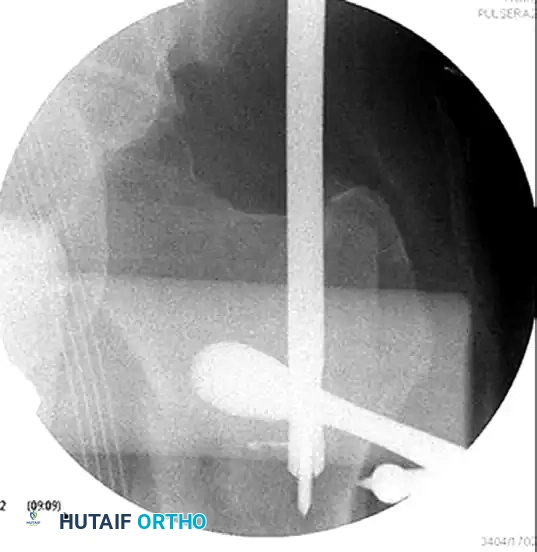

Figure C: Intraoperative AP fluoroscopic image showing the elevator and ball spike pusher actively correcting the coronal deformity.

To correct sagittal and coronal plane deformities, utilize a Cobb elevator and a ball spike pusher. The elevator can be used to lever the proximal fragment out of flexion, while the ball spike pusher controls abduction and rotation.